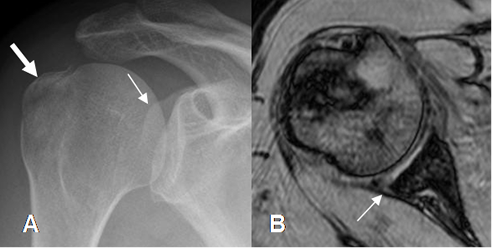

Fig 73 A. Lesión de Bankart posterior.

A: Rx AP. Luego de la reducción de una luxación posterior, se encuentra fragmento suelto en la parte posterior de la glenoides (Flecha delgada) y fractura de la tuberosidad menor (Flecha gruesa).

B: RM axial en FFE. Desprendimiento del labrum posterior permaneciendo integro el periostio, por lesión POLSA.

Fig 73 B. Lesión POLSA.

ArtroRM axial en STIR. Defecto en el labrum posterior, el cual se llena de contraste y sin ruptura del periostio, por lesión POLSA.